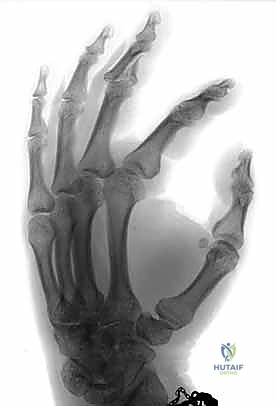

The cornerstone of diagnosis is plain radiology. Crucially, we need true posteroanterior (PA) and lateral radiographs centered specifically on the injured PIP joint. Hand radiographs alone, often taken in the emergency department, are inadequate.

Figures 5A-C emphasize that hand radiographs are only interpretable with a true lateral view of the PIP joint.

Fluoroscopy is invaluable for assessing injury dynamics and joint stability in real-time. It helps differentiate stable from unstable injuries, whether fracture-subluxations, dislocations, or pilon fractures. Subluxation and dislocation are best visualized on the lateral radiograph and can be subtle, appearing as joint incongruity or the "triangle sign" (dorsal overhang of the middle phalanx base).

Figure 4E illustrates dorsal fracture-subluxation with joint incongruity and the classic V-sign.